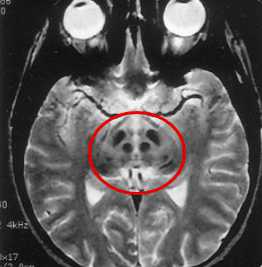

· МРТ головного мозга: более информативно в диагностике, чем КТ головного мозга. Характерны билатеральные очаги пониженной плотности 3-15 мм в диаметре в области базальных ганглиев (хвостатое ядро, скорлупа и бледный шар), в таламусе, в области зубчатых ядер и коры мозжечка - симптом «морды гигантской панды» [19]. По мере прогрессирования процесса выявляются признаки диффузного атрофического процесса головного мозга с равномерным расширением субарахноидальных пространств и желудочковой системы [20]. Изменения МР-сигнала от структур головного мозга могут отсутствовать у 7-17% детей со смешанной формой болезни Вильсона при наличии неврологической симптоматики в виде тремора, дизартрии и изменения мышечного тонуса по экстрапирамидному типу 5.

Проявления указанной патологии на МРТ выявляются благодаря повышению МР-сигнала в режиме Т2 и снижении в режиме Т1 от подкорковой области (ограды, скорлупы, хвостатых ядер, латеральных бледных шаров, наружной капсулы), среднего мозга, зубчатых ядер мозжечка и червя.

Первыми, как правило, поражаются скорлупа и хвостатые ядра. В мосту мозга распознаются поражение его срединных и дорзальных отделов с сохранностью пирамидных трактов и аналогичным изменением МР-сигнала от этих структур.

Последовательная эволюция изменений сигнала от дорзальной части моста напоминает «морду детеныша панды» с «глазами», которые формируются патологическим сигналом от центральных покрышечных проводящих путей.

Поражение среднего мозга носит диффузный характер, однако преобладает поражение белого вещества с сохранностью ядерных структур, в том числе наиболее крупных красных шаров. На поздних стадиях болезни выявляются атрофические изменения в подкорковых структурах.

Высокое качество визуализации структурных изменений в головном мозге, которое обеспечивает МР-томография, очень важна для правильной постановки диагноза. Таким образом, проявления болезни на МРТ считаются патогномоничными (т.е. безусловно характерными), что позволяет дифференцировать болезнь Вильсона-Коновалова от других неврологических патологий.